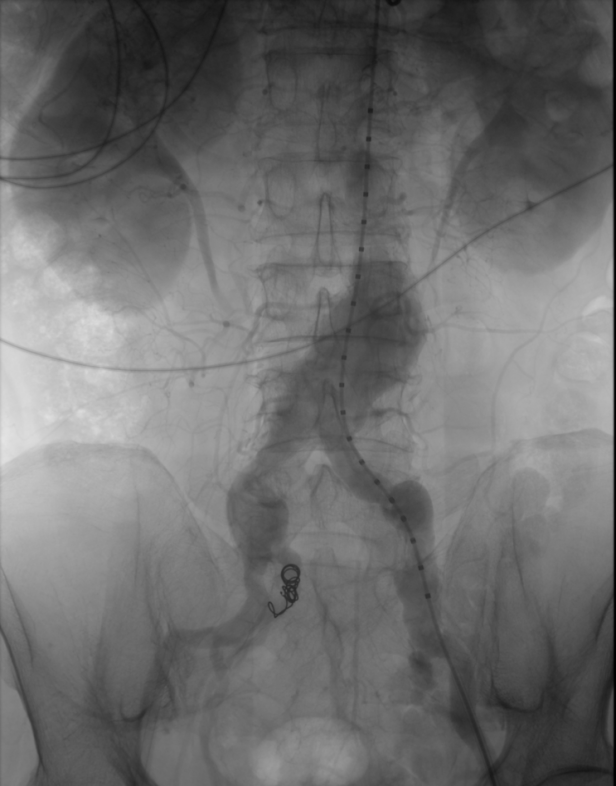

▶ 成功置放覆膜支架及可控弹簧圈

▶ 造影见动脉瘤支架完全覆盖,无内瘘形成